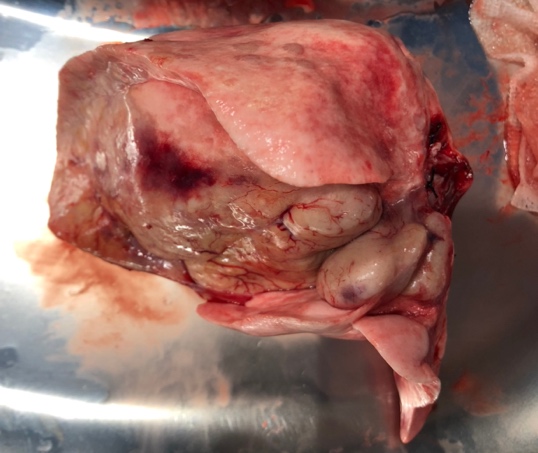

脾臓腫瘍

腫瘍が大きくなることでお腹の腫れなどを認めることがあります。また腫瘍が破裂することにより、腫瘍からの出血量によっては急性の虚脱や劇的な症状を伴うこともあります。

犬では血管肉腫が最も多い腫瘍であり、ジャーマンシェパードやレトリーバー種で発生が多いと言われています。

猫では脾臓の腫瘍は犬ほど多くはないが、猫では脾臓疾患の15%を肥満細胞腫という腫瘍が占めます。